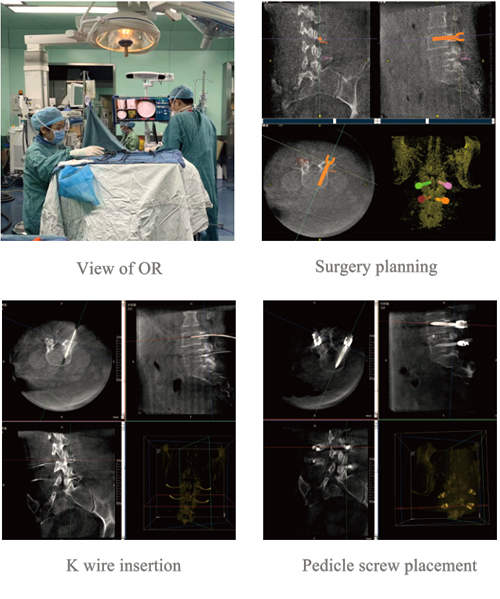

Description: Femle, 50 years old

Surgery:L4,L5 pedicle screw fixation

Numbers of screws: 4